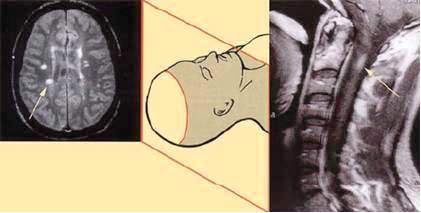

Bitna je u dijagnostici multiple skleroze, jer se njome mogu otkriti promjene

(lezije) u mozgu ili kičmenoj moždini koje upućuju na multiplu

sklerozu, a vide se kao bijela okruglasta do ovalna područja u normalno

sivom prikazu mozga ili kičmene moždine.

Te bjelkaste promjene, koje nazivamo oštećenjima ili lezijama, zapravo

najčešće prikazuju vodu koja je prodrla u područje oštećene ovojnice.

Demijelinizacijska oštećenja u multiploj sklerozi nisu podjednako raspoređena

u svim dijelovima centralnog nervnog sistema. Ona su naročito česta u

području oko moždanih komora, u dijelu mozga koji se spušta prema kičmenoj

moždini, a naziva se moždano stablo, u malom mozgu, često i u očnom nervu,

te vratnoj kičmenoj moždini. Postoji pretpostavka da su demijelinizacijska

oštećenja lokalizovana na pomenutim mjestima zbog imunološki ili hemijski

drugačije mijelinske ovojnice. Zbog navedenog razloga uvijek treba snimati

MR mozga i vratne kičme, a kod bolesnika koji imaju simptome koji odgovaraju

grudnoj kičmenoj moždini, nužno je obaviti i snimanje tog dijela kičme.

Slika MR-a mozga i vratne kičme

– demijelinizacijska oštećenja označena strelicom.